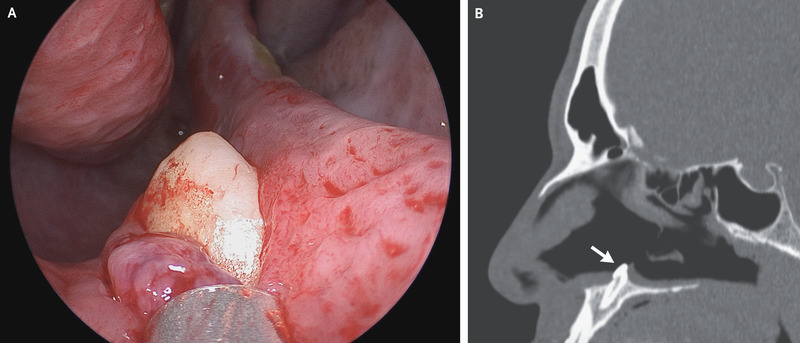

Cнимки, которые были сделаны во время обследования пациента. Фото: nejm.org